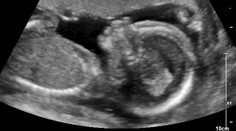

Kultúra Je to chlapec! Dojatá hviezda Harryho Pottera zverejnila fotku z ultrazvuku markiza.sk 15. 8. 2020